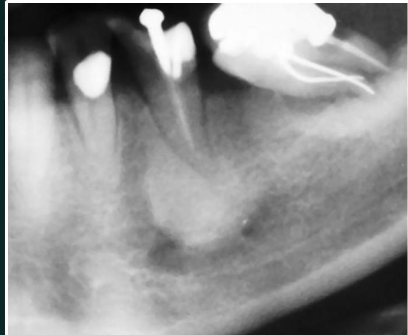

Cementoblastoma

RO mass fused to root

surrounded by RL halo

may cause expansion

may cause displacement, resorption can occur

tooth remains vital

pain may be present, but not always